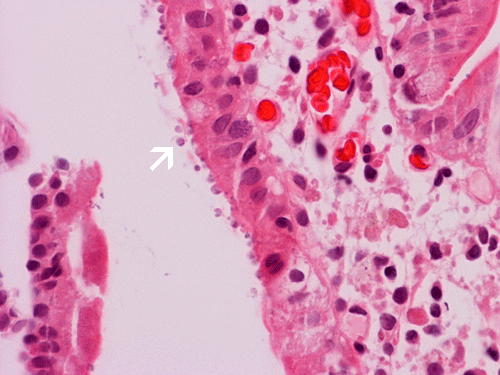

Clinical information: The patient was a 39 year-old man who was HIV (+) and presented to his doctor with the chief complaint of prolonged diarrhea. The following images are generated from biopsy obtained from the duodenum.

The mucosa is essentially quite normal other than some mild villus blunting in this case. There is no abnormal inflammatory cell infiltration. However, small bead-like organisms are lining the epithelial surface (arrows in Panel A and B). With Giemsa stain, these microorganisms are positive (arrow in Panel C) and mucin droplets are negative (arrow head in Panel C).These organisms are positive for Giemsa stain. In reality, these small organisms can be identified using medium (10X) magnification if you have a high index of suspicion.

| DIAGNOSIS: Cryptosporidiosis. |

Histologically, two salient features for diagnosis of Cryptosporidium parvum are the characteristic 2 to 5 μm, mostly extracellular, basophilic bead-like spherical bodies that typically line the surface of the intestinal epithelial cells. Cryptosporidium can be found on the surface or the crypts of the small intestine. Giemsa stain is helpful in highlighting these organisms. The mucosa may have other changes including mixed acute and chronic inflammatory cell infiltration, crypt abscess formation, villous atrophy and crypt hyperplasia. With a high index of suspicion and knowing the clinical history, Cryptosporidium can be picked up easily on medium (10X) magnification and confirmed on higher magnification. Confirmation by immunohistochemistry is helpful.